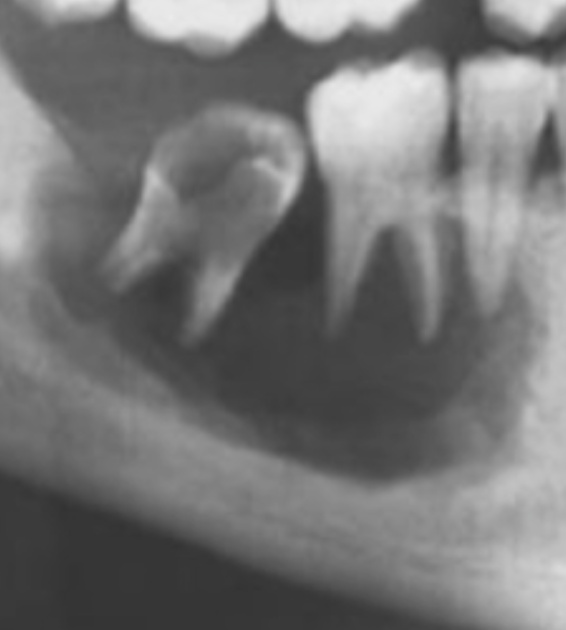

Q

A mother brought in a child with confronts that their teeth appear to be “wearing away.” An X-ray was taken revealing the following. What is the likely cause?

A

Dentogenesis imperfecta (bc you cannot see the pulp chambers)